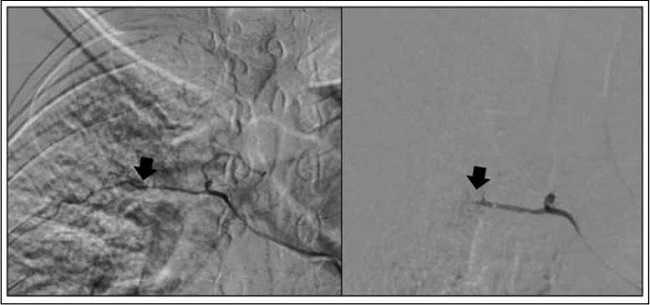

En el procedimiento se documentó arteria bronquial derecha tortuosa, ramas neoformadas que se dirigían a la caverna. Posteriormente, se realizó embolización selectiva con partículas PVA de 300 - 500 micras, con control angiográfico que demostró oclusión de los vasos intervenidos (Figura 2). Posterior al procedimiento, la hemoptisis resolvió en las siguientes 48 horas y no se presentaron complicaciones secundarias. Seis meses posteriores al evento, el paciente no presentó nuevos episodios de sangrado.

Durante la arteriografía se pudo determinar que el vaso principal comprometido es la arteria bronquial superior derecha, lo cual está en relación con la literatura, donde se describe que aproximadamente en 90% de los casos corresponde a las arterias bronquiales 4. El material descrito para embolización fue el alcohol polivinílico, siguiendo las recomendaciones actuales, dado que son agentes más estables y permanentes en el tiempo que generan mejores resultados y menos recaídas. Los agentes embolizantes más pequeños y los líquidos no han demostrado mayor efectividad ni presentan recomendación fuerte a favor de su uso 7.